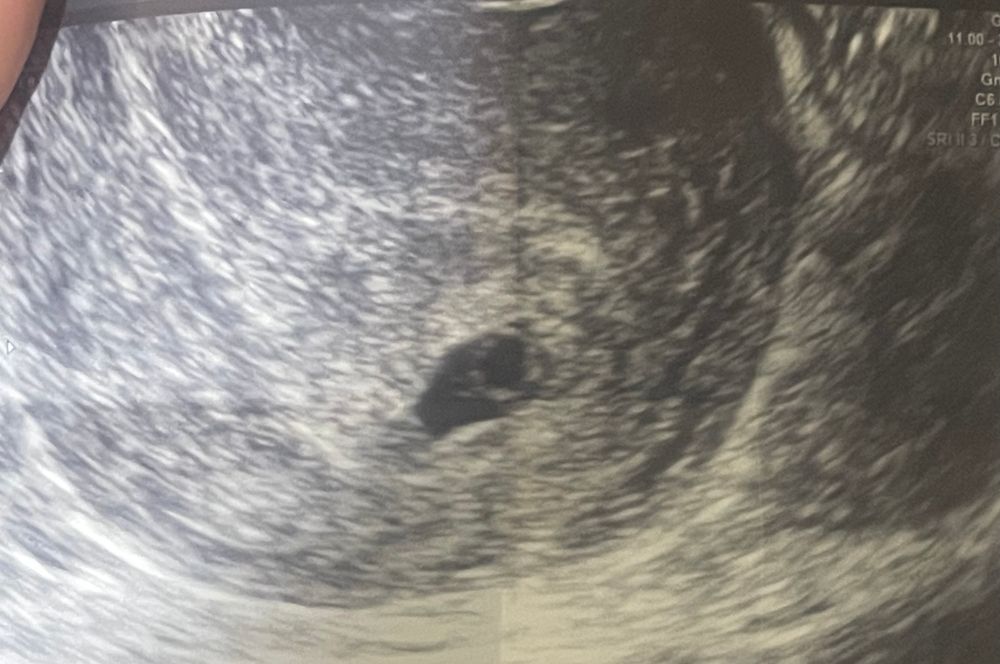

недели не эмбриона

4 5 недели не эмбриона 146 фото